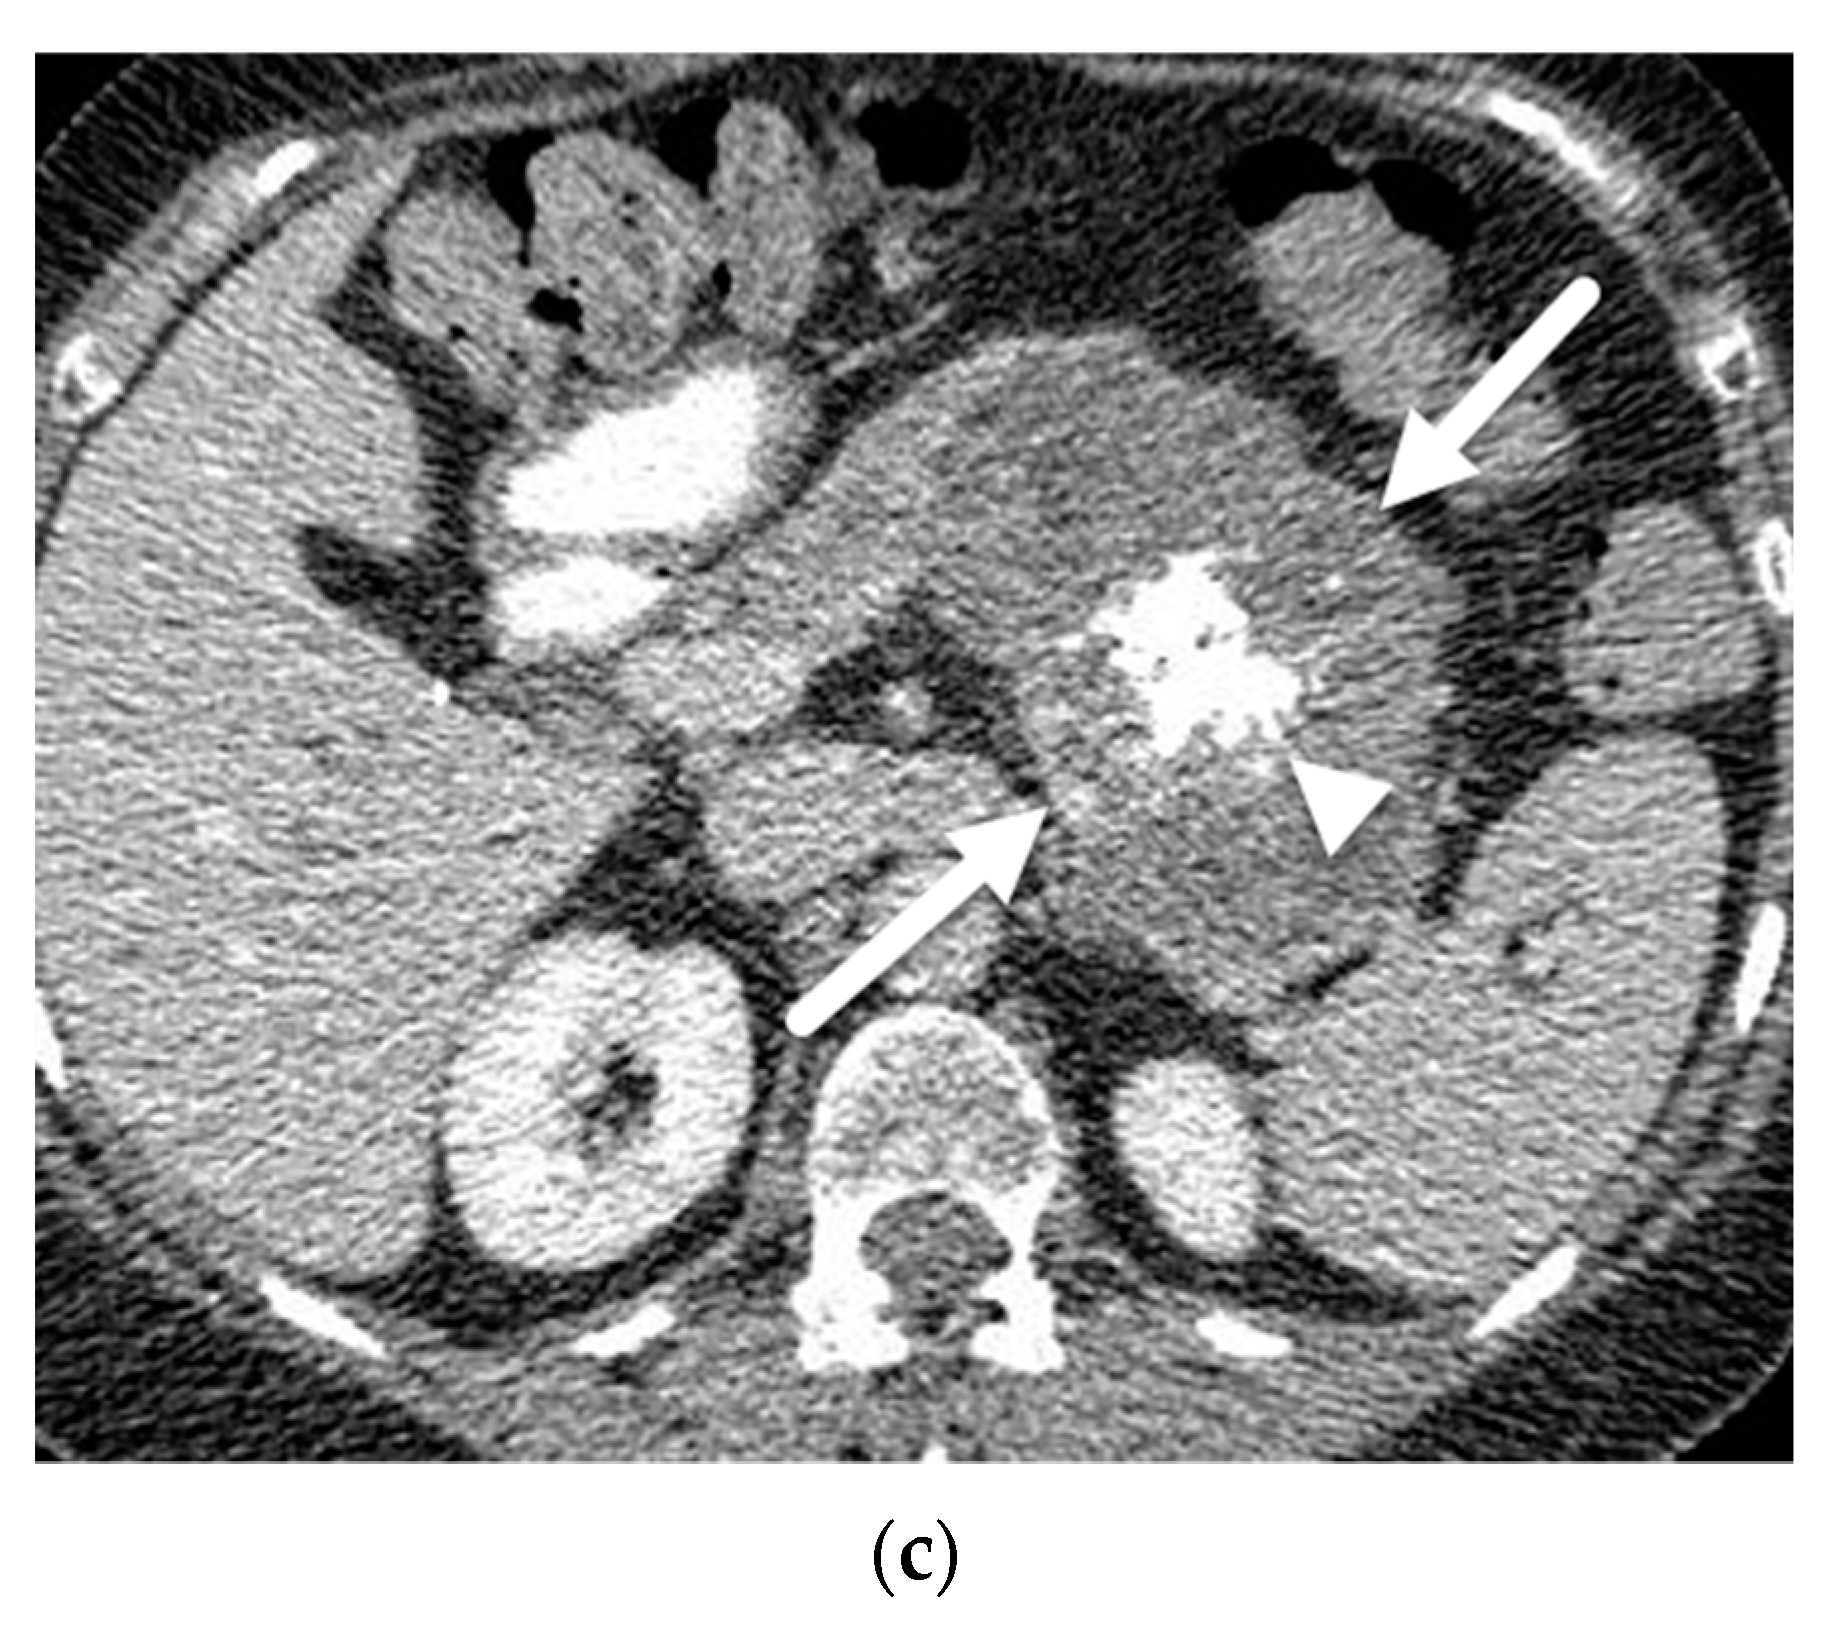

- Mamone, G.; Barresi, L.; Tropea, A.; Di Piazza, A.; Miraglia, R. MRI of mucinous pancreatic cystic lesions: A new updated morphological approach for the differential diagnosis. Updates Surg. 2020, 72, 617–637. [Google Scholar] [CrossRef] [PubMed]

- Garces-Descovich, A.; Beker, K.; Castillo-Angeles, M.; Brook, A.; Resnick, E.; Shinagare, S.; Najarian, R.M.; Mortele, K.J. Mucinous cystic neoplasms of the pancreas: High-resolution cross-sectional imaging features with clinico-pathologic correlation. Abdom. Radiol. 2018, 43, 1413–1422. [Google Scholar] [CrossRef]